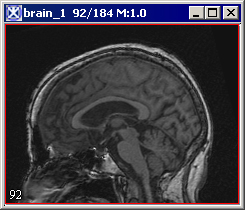

Paints the extracted brain onto the current image. See also Figure 3.

Figure 3. The Extract Brain to Paint option: on your left is the original image and on your right is the result image with the brain extracted to paint.